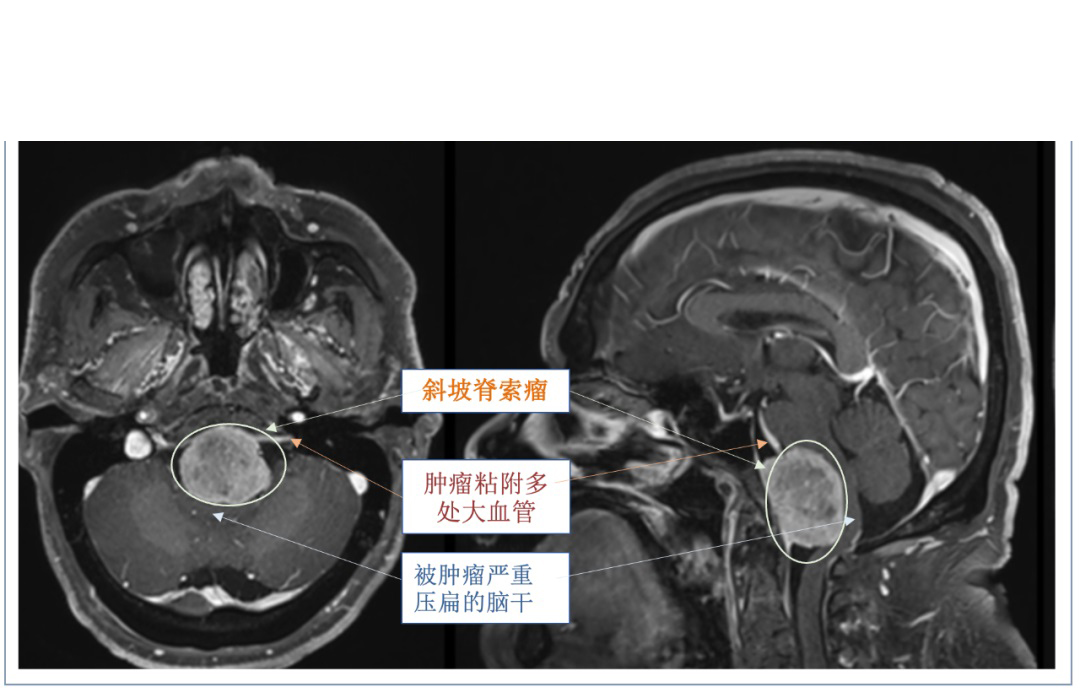

INC旗下国际神经外科顾问团(WANG)成员、国际神经外科联合会(WFNS)颅底手术委员会前主席Sebastien Froelich教授(福洛里希教授,以下简称福教授),2023年来华期间,福教授在上海INC总部与国内神经外科青年医生展开了精彩纷呈的学术沙龙,并交流了经典的手术案例。上图为一名57岁患者,该患者的核磁共振片上显示肿瘤由斜坡向后生长,突破颅底硬膜长至硬膜下,直接压迫脑干腹侧,较严重的地方脑干已被压扁至原来的三分之一。由于肿瘤的压迫效应,该患者发生头痛、吞咽困难、右侧舌头萎缩等症状。福教授在神经内镜下,通过经鼻入路成功切除严重压迫脑干腹侧的斜坡较大脊索瘤,实现镜下全切。

斜坡区脊索瘤:向前生长侵犯蝶窦、鞍区,少数累及后组筛窦;向下生长表现为鼻咽腔及周围间隙的肿块:向后生长可压迫脑干,累及颈静脉窝和枕骨大孔。斜坡脊索瘤的治疗方法包括手术、放疗和化疗。脊索瘤的浸润性和侵袭性生长特点,使得手术完全切除肿瘤仍然具有挑战性。此外,在某些情况下,大面积硬膜内切除的相关并发症(如脑干损伤、基底动脉损伤、脑脊液漏)可能会影响肿瘤完全切除。